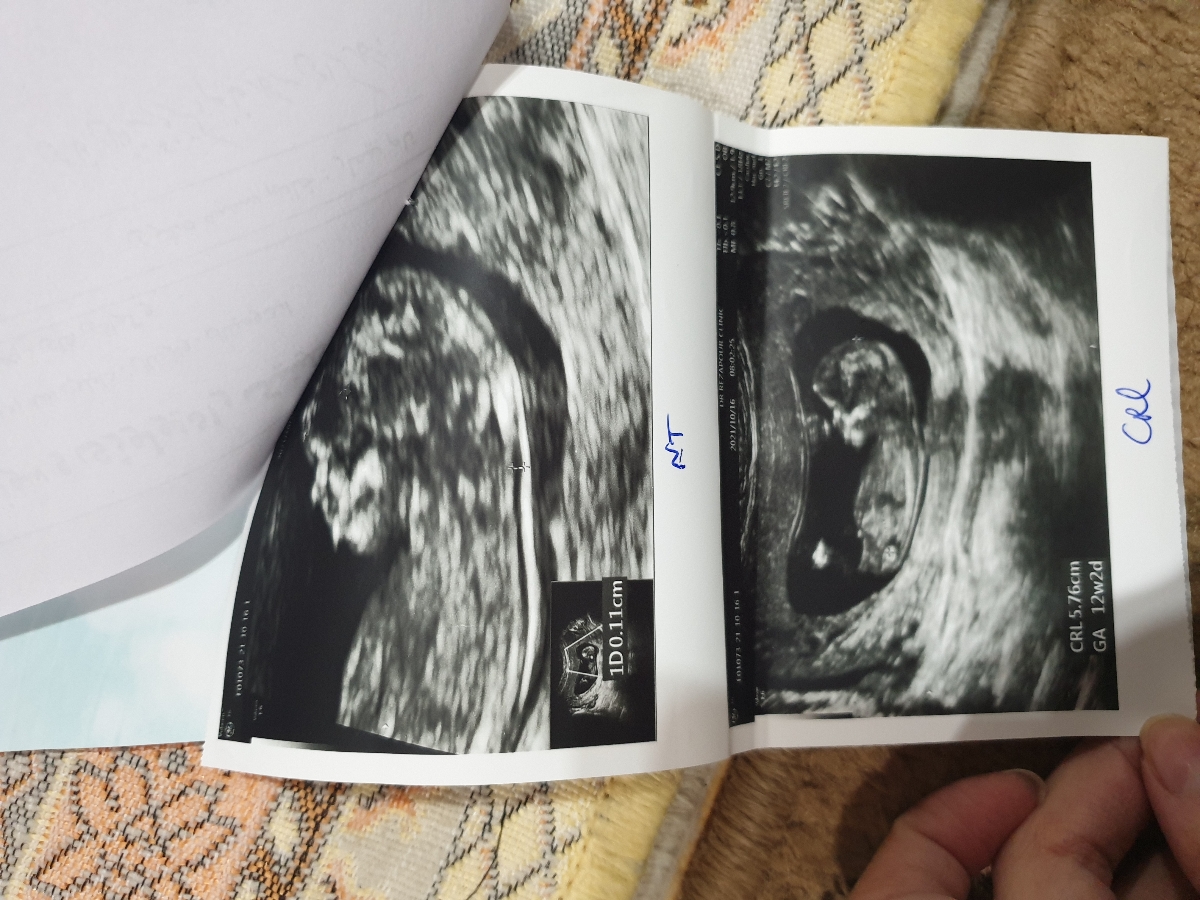

بچه ها لطفا هر کی آگاهیش تو این زمینه بالاس بگه پسره یا دختر بعضیا میگن دختره بعضیا میگن پسر ؟

اخه بگم چی دکتر توی سونوگرافی احتنال دختر داد امروز رفتم پیش دکتر خودم که ازمایشمو نشون بدم صدای قلبشو گوش داد گفت احتمال میدم پسره اصلا گیج شدم

بیشتر از این تصویر گفتم

مثل عکس پایینیه

شمام عکس سونو آن تی رو لطفا بفرستید😁